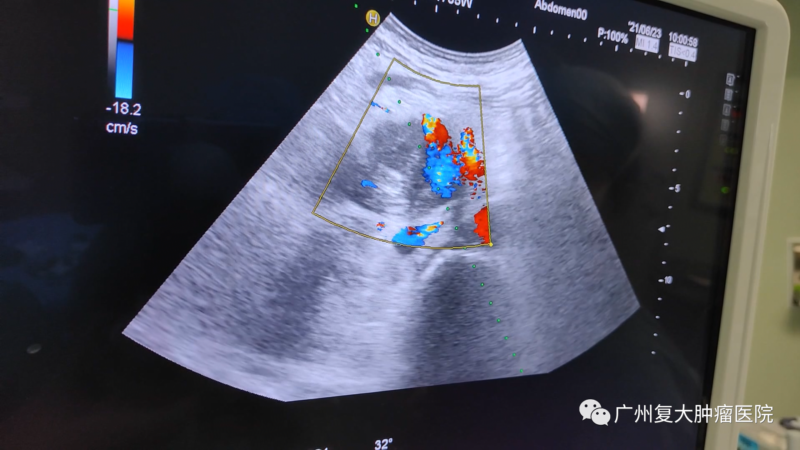

針對(duì)劉叔的病情,我院牛立志院長(zhǎng)為他實(shí)行胰腺及肝臟轉(zhuǎn)移瘤穿刺活檢+胰腺及肝臟轉(zhuǎn)移瘤納米刀消融術(shù)。在超聲+CT引導(dǎo)下,全程監(jiān)測(cè)、設(shè)計(jì)布針路線(xiàn)、避開(kāi)重要的血管,將“納米刀”精準(zhǔn)植入腫瘤,以達(dá)到減輕腫瘤負(fù)荷,減緩疾病進(jìn)展的效果。

影像(如超聲、CT等)引導(dǎo)下經(jīng)皮納米刀消融,無(wú)需開(kāi)腹,只需幾個(gè)針尖大小的小孔,達(dá)到殺滅腫瘤的效果,減輕病人痛苦。在影像設(shè)備的輔助下,可以對(duì)納米刀探針的定位、標(biāo)靶區(qū)域的消融過(guò)程以及最終消融區(qū)的大小進(jìn)行實(shí)時(shí)監(jiān)控,且影像中消融區(qū)邊界的精確度可與組織學(xué)上的精確度相媲美。另外,實(shí)時(shí)監(jiān)測(cè)還可以讓醫(yī)生觀(guān)察到消融區(qū)周?chē)M織的變化,從而推斷出并發(fā)癥出現(xiàn)的可能性,保障病人的安全以及有助于其術(shù)后快速恢復(fù)。

影像設(shè)備實(shí)時(shí)監(jiān)控